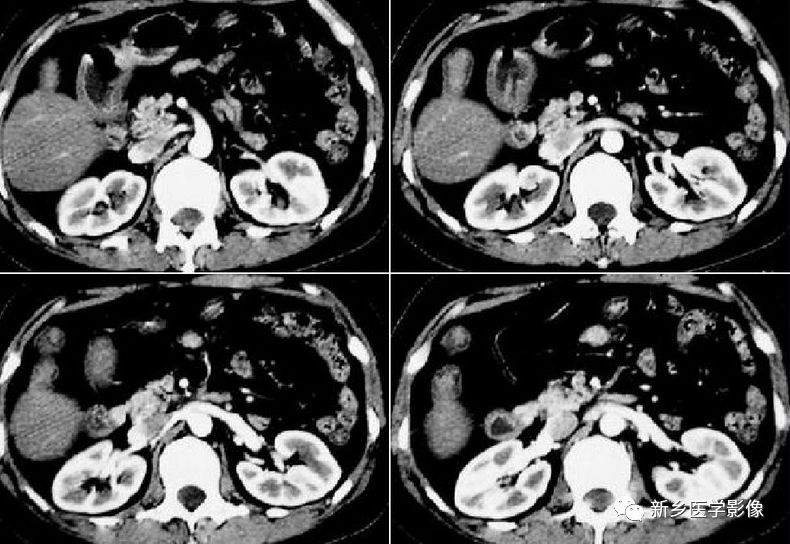

肝左叶缩小常见,左侧缘不超过中线左侧;动脉期可见一过性灌注异常,门静脉期及平衡期与右叶同步强化,其内血管分布正常。鉴别诊断:术后改变;慢性期肝梗死;创伤后期、慢性门静脉或胆管阻塞;严重营养不良。

肝右叶缺如居多,多合并胆囊缺如,左叶代偿性增大,密度均匀,常合并肝内胆管轻度扩张;增强扫描门静脉主干及左支增粗,右支不显影。鉴别诊断:术后改变;肝硬化;创伤。